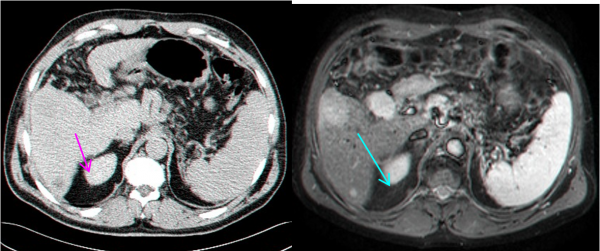

- MRI הוא אמצעי טוב להדגמת השאתות, מקומן האנטומי ויחסן לכלי הדם בכבד (תצלום 34.10). נמצא שה- MRI הוא יותר רגיש ויותר ספציפי ביחס ל- CT, אולם יותר יקר ממנו.

בחלק מהחולים ניתן לשלב את טיפול הכריתה עם טיפול הורס של גרורות (ראה טיפולים מקילים). בחולים עם גרורות בודדות באונה השנייה, או בחולים עם סיכון ניתוחי גבוה, ניתן להרוס את הגרורות על ידי אמצעים תרמיים. מצויות היום אלקטרודות מיוחדות שניתן לכוונן למרכז הנגע בכבד ודרכם להעביר אנרגיית חום על ידי חימום או גל רדיו (Radio frequency) או הקפאת השאת ובכך לחסל את גרורה (תמונה 11.10-12.10). בשיטות אלה ניתן להשתמש כאשר קוטר הגרורה קטן (פחות מ- 3 ס"מ) ובחולים עם גרורות בודדות. לעיתים, ניתן לשלב את הכריתה הכירורגית עם הרס תרמי של הגרורות, לדוגמה כריתת אונה מחד גיסא והרס תרמי של הגידול נותר מאידך גיסא.